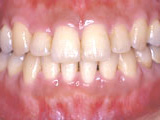

症例1:乱杭歯「歯並びが乱れている」

治療前

治療後